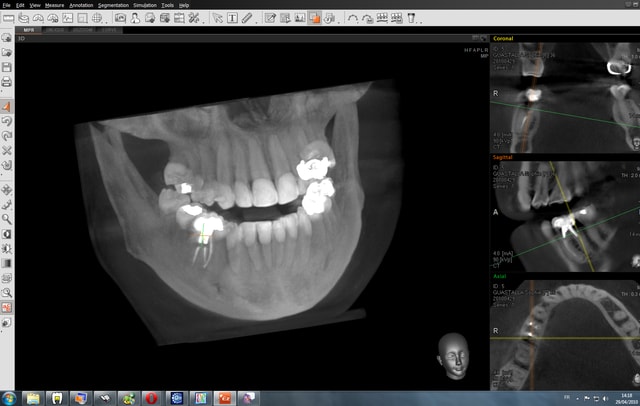

J'en possède une (duo 3D) depuis avril.

Trés bon appareil, taille de champ variable de 5x5 à 12.5x8 Pano de bonne qualité, logiciel de planification trés bon.

Qualité d'image en 3d superbe...